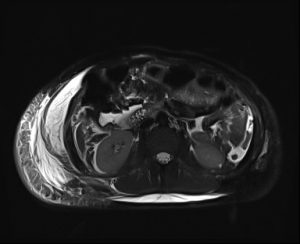

An MRCP was performed next, that showed intact common bile duct and intact cystic duct stump. Also, an area of fluid accumulation was noted in the subhepatic space, intraintestinal and in the small pelvis. Subcutaneous oedema in the right lateral abdominal wall was also noted, most likely post operatively.

An indication for postoperative laparoscopic revision was made where a larger biliary collection was found in the abdomen that was aspirated, and after a thorough exploration of the gall bladder bed, an aberrant bile duct smaller than 1mm was observed that is a Luschka subvesical duct, which secreted bile with an extremely small content. A biliary stasis was performed with a ligation of the aberrant Luschka duct using sutures and two intraperitoneal drains were placed for drainage. The postoperative course was in order. The control CT of the abdomen and pelvis after 2 weeks showed complete resorption of the free fluid in the abdomen and pelvis. In the region of the gall bladder fossa, several more air inclusions were observed, which would be in favor of a normal postoperative reaction. The patient was discharged for home treatment in good general condition with advice given for a hygiene-dietary regimen and antibiotic therapy according to the protocol for operated patients.